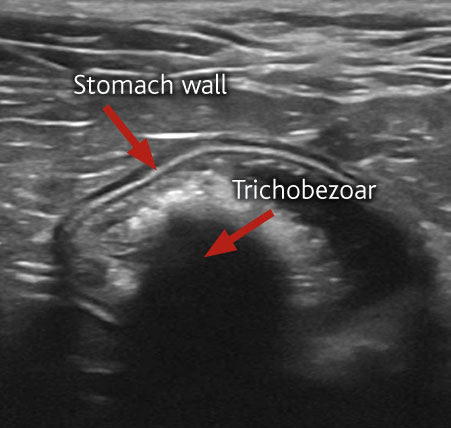

The ultrasound scan revealed Jaffa’s problem to be a Trichobezoar, which is a mass of hair, blocking the exit of his stomach and preventing food from passing through into the intestines.